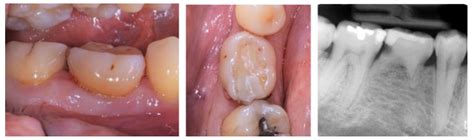

Radiographic Features of Mandibular Second Molars with Eruption ...

mdpi.com